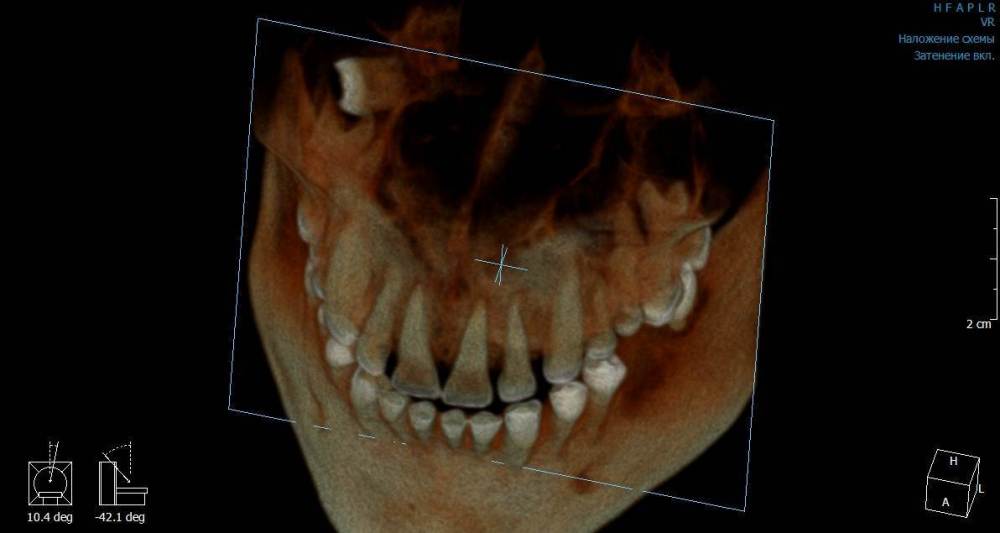

Mnrg Опубликовано 7 июля, 2023 Автор Поделиться Опубликовано 7 июля, 2023 6 минут назад, wladdX сказал: Гайморит у вас совершенно необязательно имеет одонтогенную природу (вызван зубами). Судя по КТ, зуб 16 может быть виновником (а может и не быть). Для уточнения нужна также проверка витальности его пульпы (жив нерв или нет). Если пульпа нежизнеспособна, то этот зуб почти наверняка поддерживает воспалительный процесс в пазухе. Зуб 18 вряд ли нужно трогать. Лежит он себе в кости и пускай, никому он там не вредит. Да он вплотную прилежит к корням зуба 17, но и только. С внешней средой не контактирует. Никакого негативного влияния на соседние зубы он оказывать не должен: формирование корней завершено, потенции к росту и какому-либо движению нет. Удаление зуба 18 в данной ситуации вряд ли оправдано. Процедура не самая простая, но и не запредельной сложности. Шестерку проверяли холодом - чувствует, не знаю, означает ли это жизнеспособность пульпы, но на холод реагировал немного сильней других зубов. Сегодня открыл КТ программой RadiAntViewer и обнаружил в 3D просмотре визуальные признаки нахождения части восьмерки в краю пазухи. Конечно я не могу утверждать, т.к не врач и насколько понимаю это режим моделирования, но все же выглядит убедительно на мой скромный взгляд. Еще один глупый вопрос, если позволите) Возможно ли в шестерке в одном из трех корней воспаление и нерв разрушен, а другие два при этом будут создавать чувствительность, т.е быть "живыми" или же это фантастика? Деньги запросили немалые для нашего региона за депульпацию (13к) поэтому пытаюсь собрать как можно больше информации прежде, чем принимать решения. Ссылка на комментарий